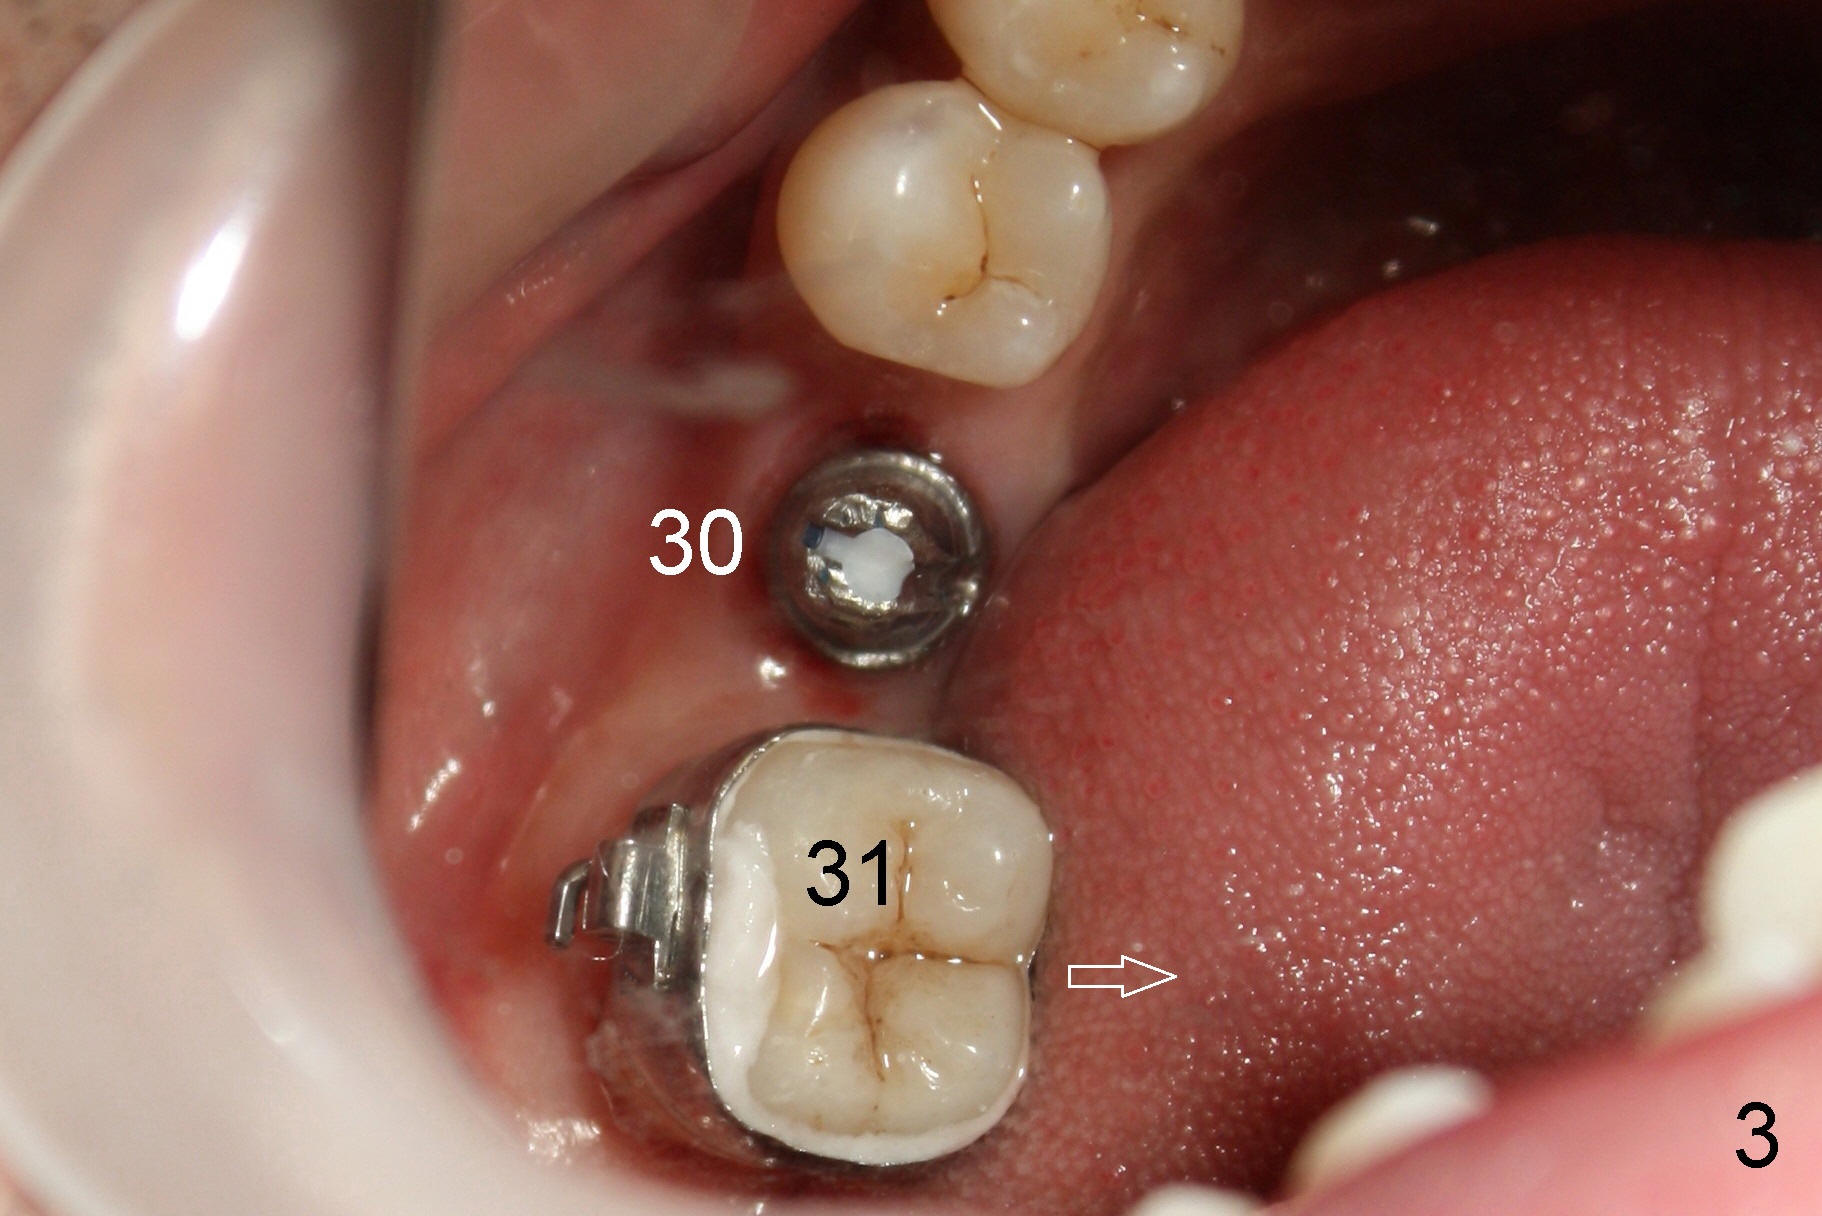

A 50-year-old man has lost the lower right 1st molar for several years (Fig.1: 30). The 2nd molar has shifted (arrow) and inclined (white line) mesially. It does not appear to occlude with the tooth #2 in this panoramic X-ray. It is planned to place an implant at the site of #30 and after osteointegration to use it as an anchorage to upright and distalize the tooth #31. Four and a half months after placement of a Tatum tapered implant (6x17 mm), a 5 mm 10 degree unipost ((short) abutment) is placed and prepared for temporary crown (Fig.2: A). Severe cross bite (overjet) is noted between the teeth #2 and 31. It is due to combination of the lingual inclination of the tooth #31 (Fig.3 (mirror view) arrow) and the buccal displacement of the tooth #2 (Fig.4 mirror image).

A molar band is placed for #31 and a bracket for #2 (Fig.5). A temporary crown (#30) is cemented with an intention to raise the occlusion. Notice the space between upper and lower premolars (between 2 arrowheads). There is also a space between #2 and 31. One to three elastic bands are placed between the buccal hook of #2 and the lingual cleat of #31 (Fig.5,6). One months passes without correction of the molar cross bite. More bands and brackets are placed in the upper and lower right posterior sextants (Fig.6). With combination action of elastics and segmental wires, the inclination of the tooth #31 is not only corrected buccolingually (blue arrow), but also mesiodistally (black arrow, uprighting). The implant crown is mainly used as an occlusal stop; because of constant wear, composite is being added (*) to its occlusal surface of the temporary crown to keep posterior occlusion open (let #2 and 31 move freely). In this case the implant is in fact not used as a pure anchorage to distalize #31 due to difficulty in placing an open coil spring between #30 and 31 tubes. The alignment of the upper right sextant improves under the tension (bending) of the wire (Fig.7 white arrowhead). The tooth #2 is being moved lingually. In fact, elastics are also placed between #3 lingual cleat (yellow arrowhead) and #30 buccal hook to improve #3 buccolingual position and/or inclination (compare Fig.4 and 7).